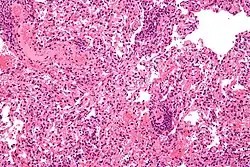

| Micrograph showing lung transplant rejection. Lung biopsy. H&E stain. | |

Diagnosis of acute rejection relies on clinical data—patient signs and symptoms but also calls on laboratory data such as blood or even tissue biopsy. The laboratory pathologist generally seeks three main histological signs: (1) infiltrating T cells, perhaps accompanied by infiltrating eosinophils, plasma cells, and neutrophils, particularly in telltale ratios, (2) structural compromise of tissue anatomy, varying by tissue type transplanted, and (3) injury to blood vessels. Tissue biopsy is restricted, however, by sampling limitations and risks/complications of the invasive procedure.[31][32][33] Cellular magnetic resonance imaging (MRI) of immune cells radiolabeled in vivo might—similarly to Gene Expression Profiling (GEP)—offer noninvasive testing.[34][35]